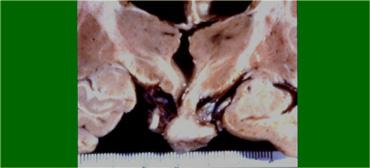

Đây là ví dụ về một túi phình huyết khối hóa một phần nằm trong bể trên yên (suprasellar cistern).

Lòng mạch còn thông (patent lumen) có tín hiệu đen trên các chuỗi xung T1W này.

Xung quanh lòng mạch là các lớp cục máu đông ở nhiều giai đoạn khác nhau, sắp xếp thành từng lớp từ lòng mạch đến thành túi phình.

Hình ảnh này trông giống như một củ hành tây cắt đôi.

Bên trái là mẫu bệnh phẩm tử thiết.

Có thể thấy bệnh nhân này bị xuất huyết não thất và xuất huyết dưới nhện (subarachnoid hemorrhage) diện rộng.

Các lớp cục máu đông được phản ánh rất rõ nét trên hình ảnh MRI.